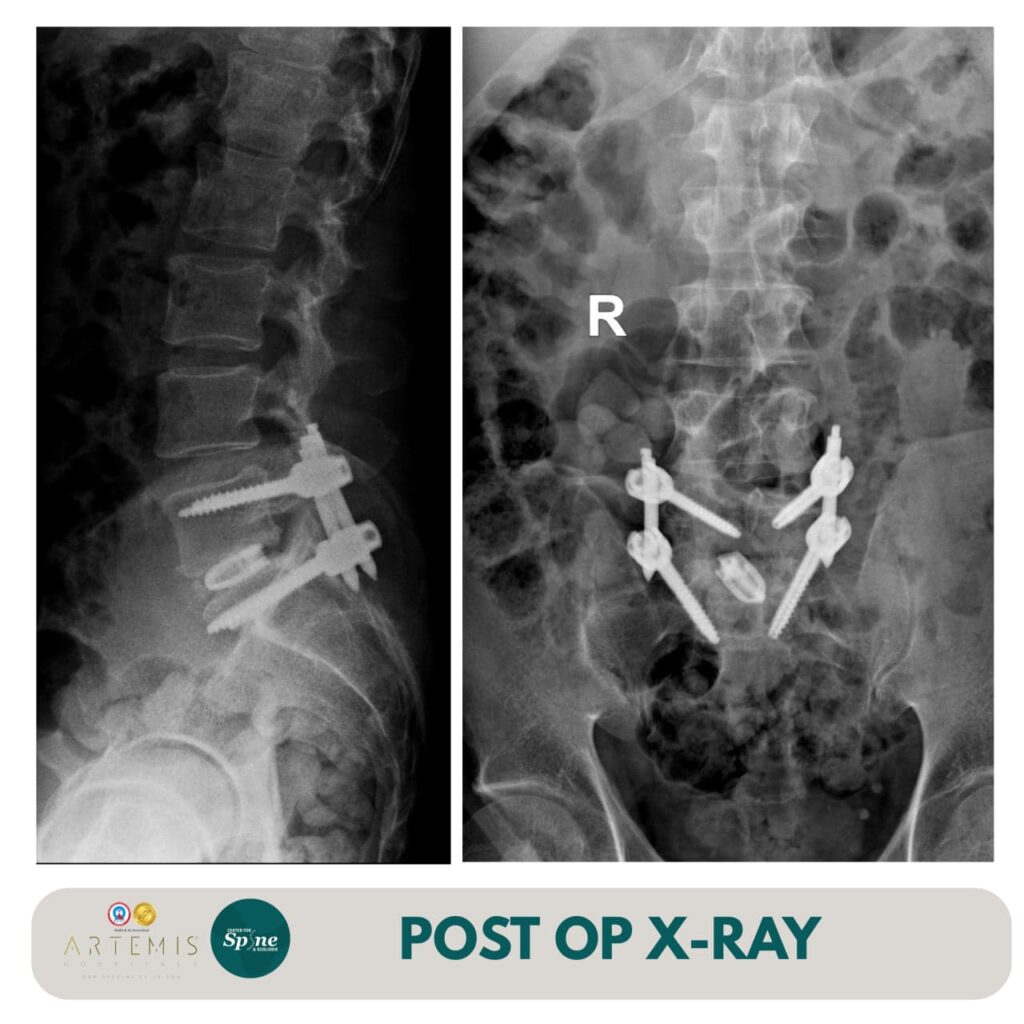

Given the acute neurological deficit and severity of symptoms, the patient was advised Minimally Invasive Transforaminal Lumbar Interbody Fusion (MIS-TLIF) at L5–S1. This advanced spine surgery technique enables effective nerve decompression and spinal stabilisation with minimal tissue disruption, reduced blood loss, and faster recovery.

The surgery was performed successfully, achieving optimal decompression of the affected nerve root and stabilisation of the spinal segment. Postoperatively, the patient experienced significant relief from radiating leg pain and gradual improvement in motor strength. With structured rehabilitation and expert post-operative care, his recovery progressed smoothly.